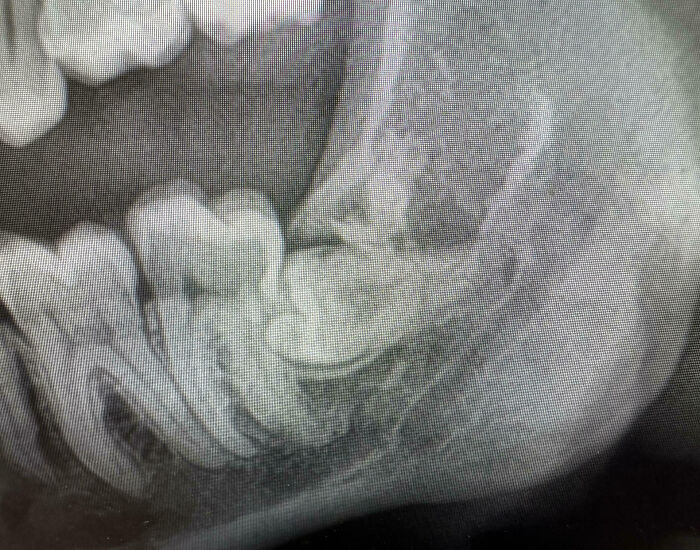

Mi muela del juicio es tonta